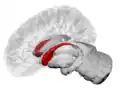

Caudate nucleus within the skull

Together with the putamen, the caudate forms the dorsal striatum, which is considered a single functional structure; anatomically, it is separated by a large white matter tract, the internal capsule, so it is sometimes also referred to as two structures: the medial dorsal striatum (the caudate) and the lateral dorsal striatum (the putamen). In this vein, the two are functionally distinct not as a result of structural differences, but merely due to the topographical distribution of function.